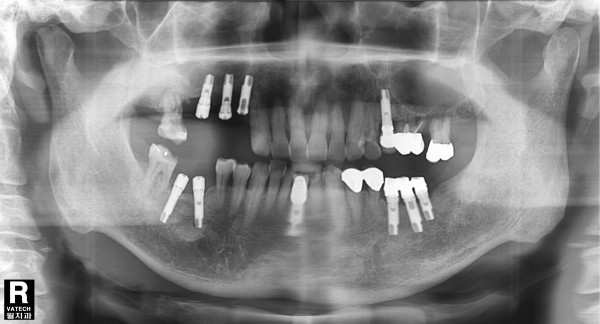

69세남자 좌측상악 상악동거상술및임플란트식립